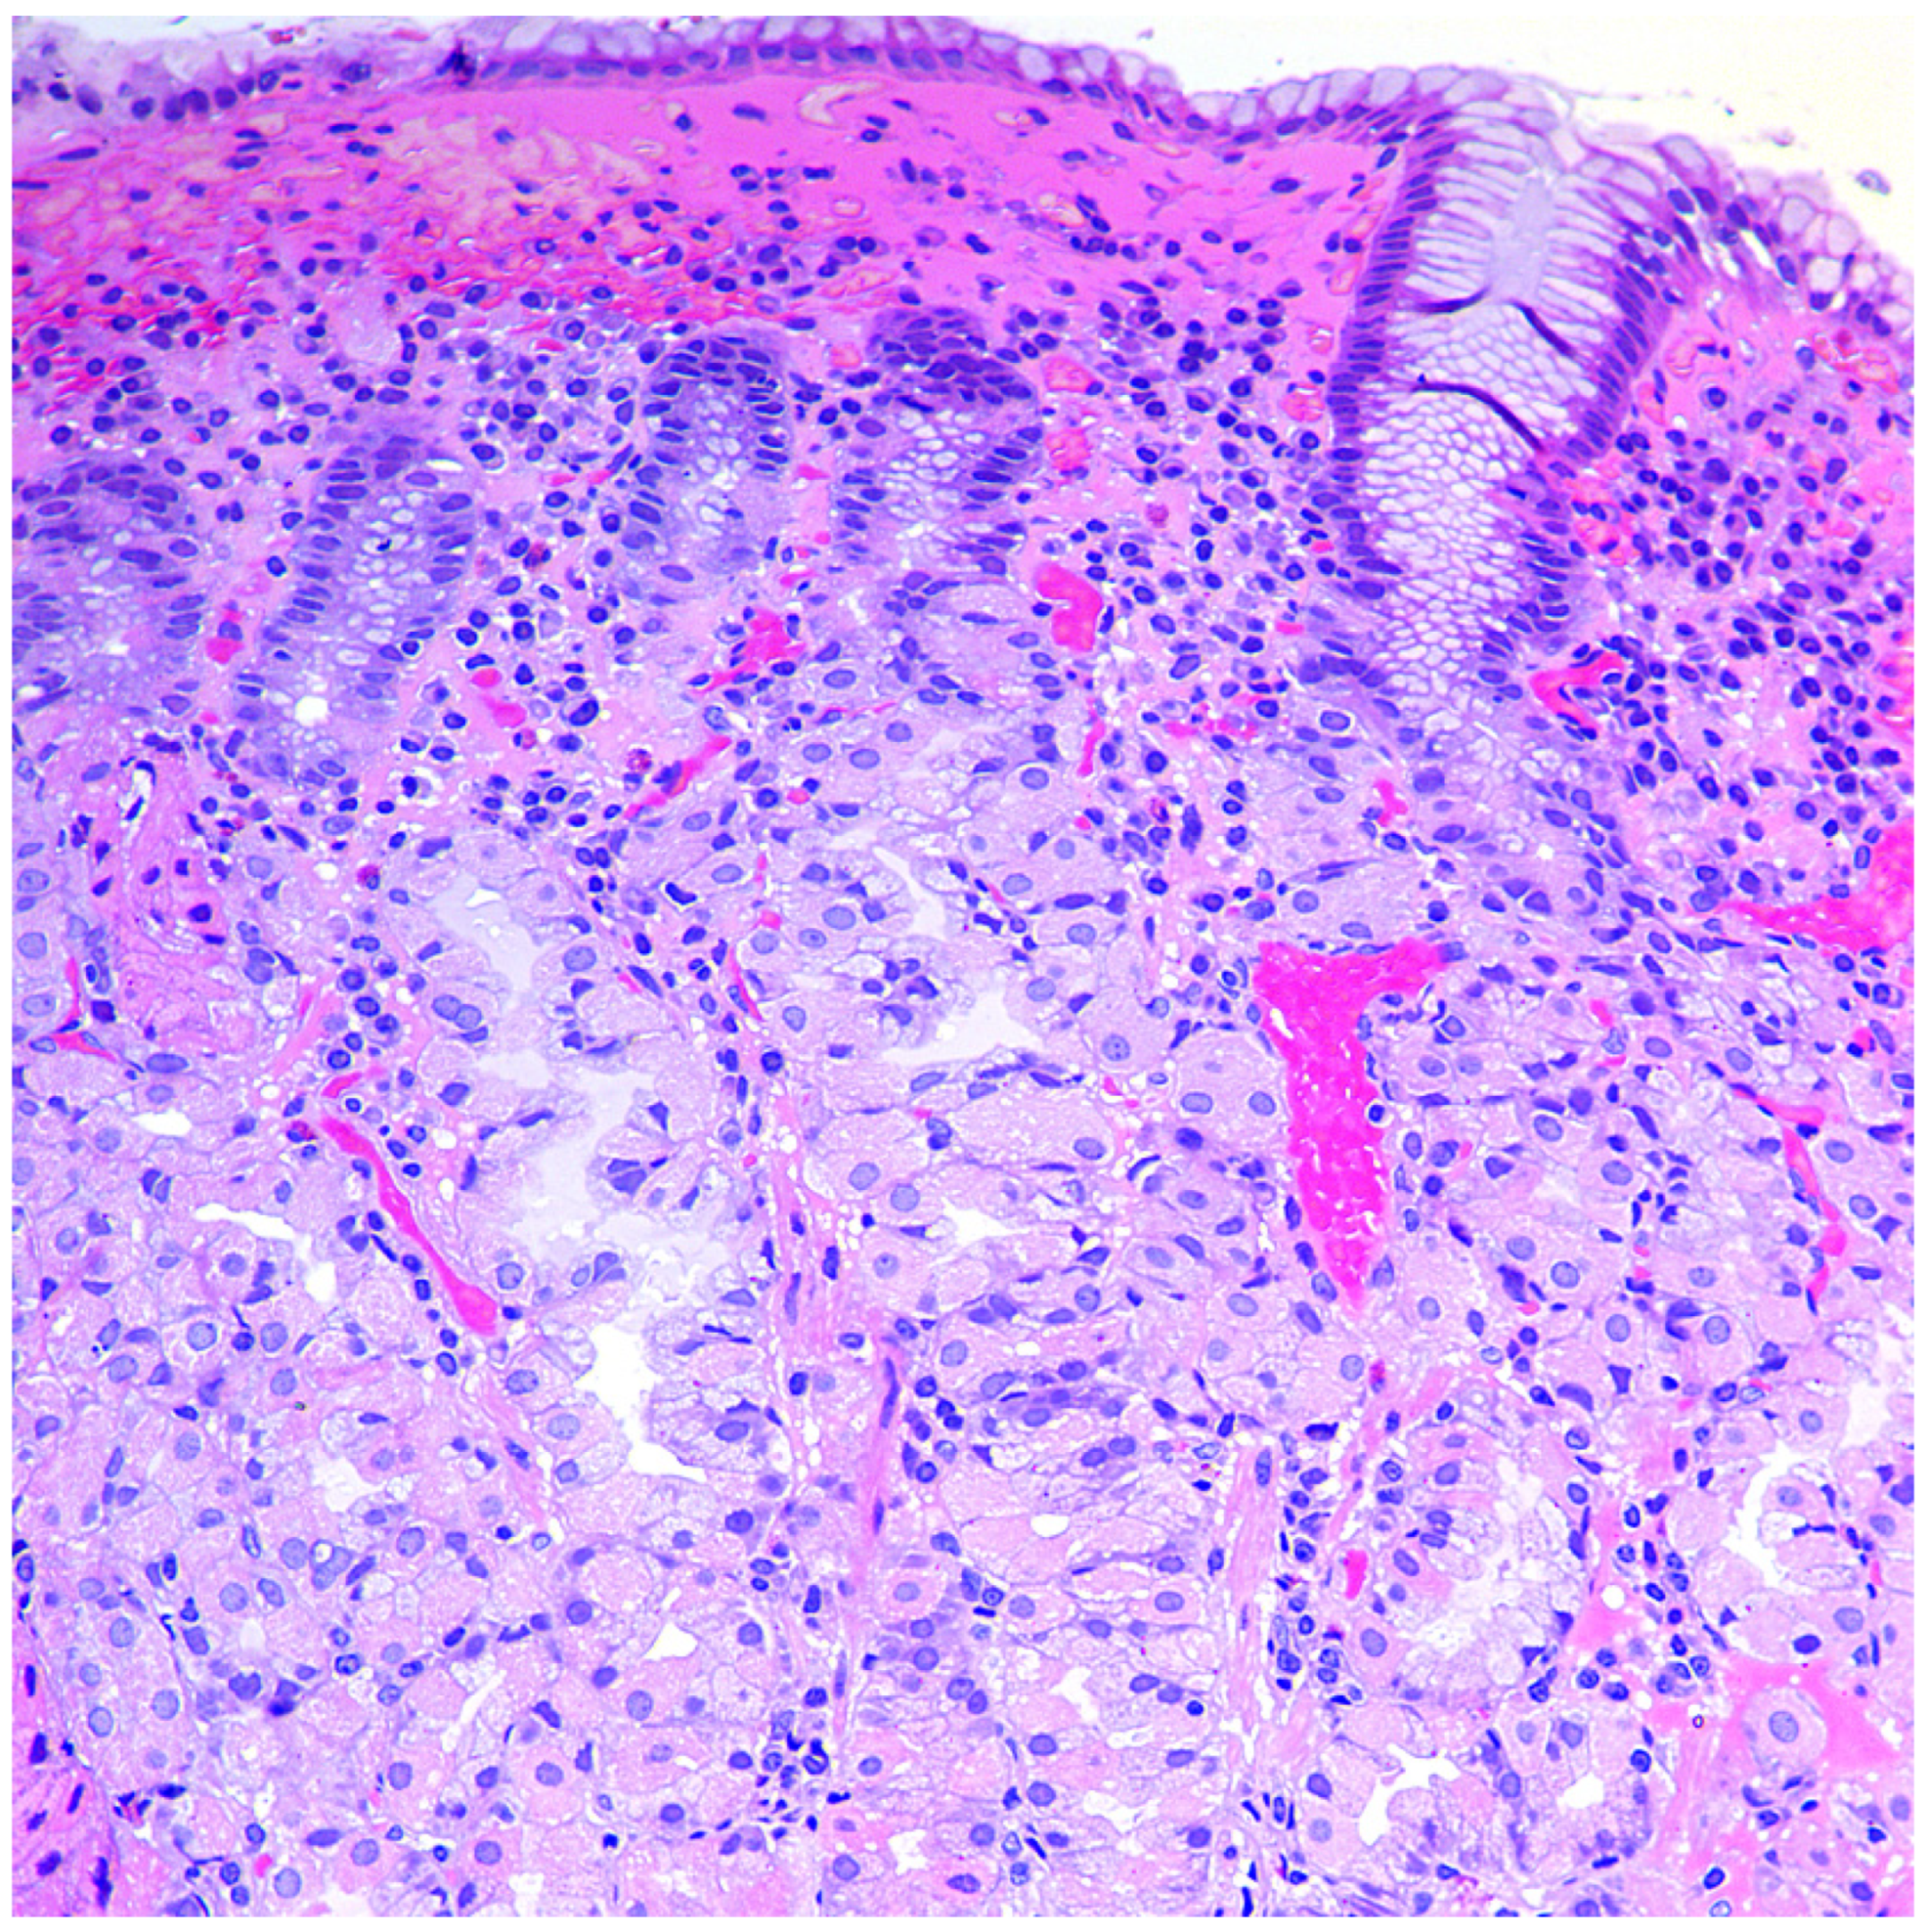

In the mucous membrane of the stomach’s body, a wide range of atrophic changes (from minimal signs of inflammation to severe atrophy of the glands) can be detected, characterized by varying degrees of the acid-producing glands’ damage, as well as the development of intestinal, pyloric (pseudopyloric metaplasia), and ECL cell hyperplasia. The process of restructuring the mucous membrane can be divided into three stages or phases. In the first, initial stage, there is a diffuse or multifocal infiltration of the lamina propria of the mucous membrane by lymphocytes and plasma cells up to the formation of pronounced infiltration and involvement of the entire thickness of the mucous membrane, often with an admixture of eosinophils and mast cells (Figure 1). Focal destruction of individual glands by components of the inflammatory infiltrate takes place. Hyperplasia of parietal cells is also characteristic, reflecting the state of hypergastrinemia. At this stage of the disease, intestinal metaplasia is rare and focal [42,43].

Figure 1.

Autoimmune gastritis: initial stage. Biopsy from the gastric body. Lymphoplasmacytic inflammatory infiltration of the lamina propria with damage to the fundic glands. Hematoxylin and eosin stain. ×200 (from the personal archive of Professor S.I. Mozgovoi).